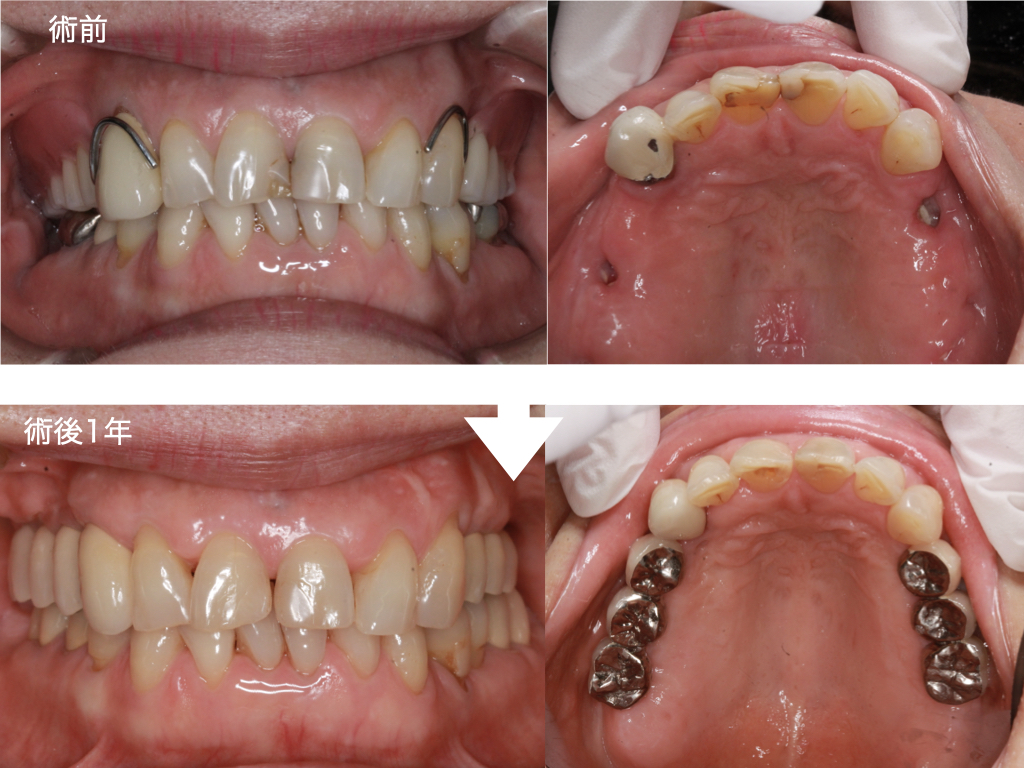

本日は、歯周病により上顎の奥歯を失い、入れ歯でお困りだった60代女性の患者さまにインプラント治療を行った症例をご紹介いたします。

上顎の左右臼歯部(奥歯)に3本ずつ、合計6本のインプラントを埋入し、奥歯の強固な噛み合わせを構築しました。

本症例のように「前歯しか残っていない状態」において、よく噛める入れ歯を作製することは力学的に非常に困難です。さらに、入れ歯のままの状態でいると残存している前歯に過度な負担がかかり、連鎖的に前歯まで悪くなってしまうリスクが高まります。

このようなケースでは、インプラント治療によって奥歯に安定した噛み合わせを確立することで前歯への負担を大幅に軽減し、口腔内全体の健康を長期的に維持することが可能となります。

歯周病治療を行った後、上顎両側臼歯部に合計6本のインプラント埋入を行いました。 現在は、定期的なメインテナンスに移行しております。